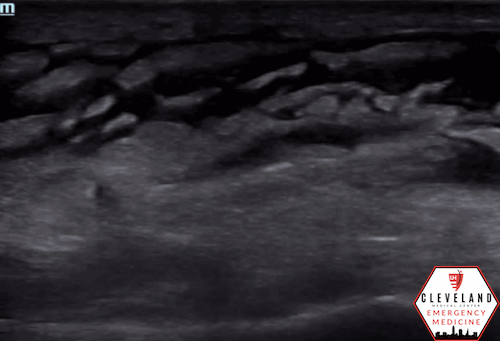

• Early: thickened skin and increased echogenicity with loss of distinct soft tissue layers (see Figure 3).

Figure 3. Early cellulitis (left) versus normal [8]